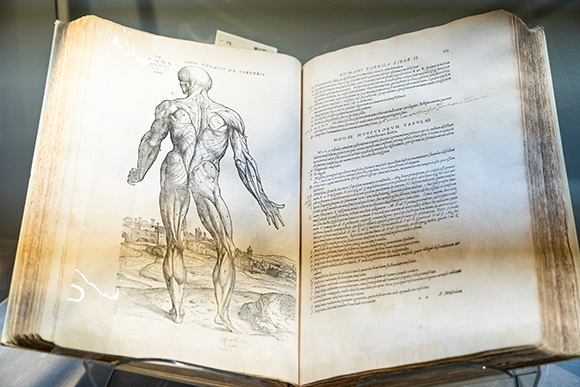

לאות שהחוקרים מדדו הם קראו “אות התלוי ברמת החמצון של הדם”. תמונת MRI של מוח בו באזור האונה העורפית מסומנים בצבעים חמים ווקסלים בהם היה שינוי משמעותי של אות הBOLD בתנאי הניסוי לעומת מצב המנוחה | Living Art Enterprises / Science Photo Library